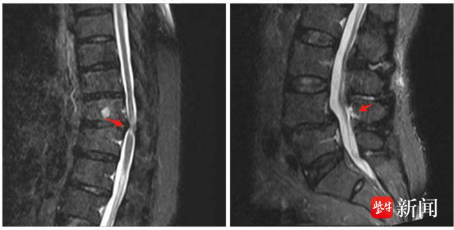

隨后,瑞康醫(yī)院骨科為患者安排了完善的影像檢查,果斷揭示了隱藏在胸椎段的“定時(shí)炸彈”——胸椎管狹窄。這是一種極具風(fēng)險(xiǎn)的疾病,若未及時(shí)干預(yù),易導(dǎo)致癱瘓甚至終身殘疾。因病灶波及胸腰段,手術(shù)復(fù)雜度陡然上升,且胸椎手術(shù)后發(fā)生神經(jīng)損害的風(fēng)險(xiǎn)遠(yuǎn)高于腰椎單節(jié)段病變。

為確保手術(shù)安全,朱鋒教授團(tuán)隊(duì)聯(lián)合麻醉科、康復(fù)科等多學(xué)科力量,充分運(yùn)用醫(yī)院配備的術(shù)中導(dǎo)航系統(tǒng)、超聲骨刀等先進(jìn)設(shè)備,精準(zhǔn)定位、精準(zhǔn)切削,成功為患者完成了胸椎減壓+腰椎融合的高難度手術(shù)。